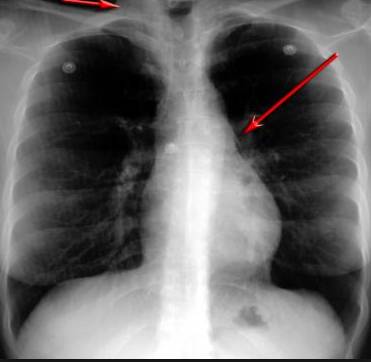

并且,因?yàn)楹粑到y(tǒng)結(jié)構(gòu)復(fù)雜,在體檢時(shí)醫(yī)生很難通過一種檢測手段,判定早期患者的病情。

使用這臺(tái)掃描儀,將直接把器官變成3D圖形!細(xì)微的毛細(xì)血管,幾毫米大的肺泡和支氣管,都將能看的一清二楚!

你的每一個(gè)氣泡,每一段支氣管,哪兒有病變都清清楚楚的將展示在醫(yī)生面前!

也就是說在一切都還沒開始惡化前,把這些有問題的器官組織都暴露的一清二楚:

這臺(tái)儀器不僅僅是一臺(tái)能拯救幾百萬條生命的高清掃描儀,它更是一場開天辟地的技術(shù)革新!因?yàn)樗粌H能幫醫(yī)生看到肺病的結(jié)構(gòu)圖,

還能看到器官是如何運(yùn)動(dòng)的!

空氣是如何進(jìn)入到肺部,氧氣是如何到血液,任何微小的變化都將曝露在醫(yī)生面前!更清晰的圖像,更細(xì)節(jié)的變化!

沒有這項(xiàng)新技術(shù),醫(yī)生在做體檢的時(shí)候,很難通過一種測試斷定一個(gè)人是否有呼吸系統(tǒng)疾病。

可是現(xiàn)在他們不但能看到整個(gè)肺部的3維結(jié)構(gòu)圖。還能看到空氣進(jìn)入人體后的所有微小變動(dòng)!